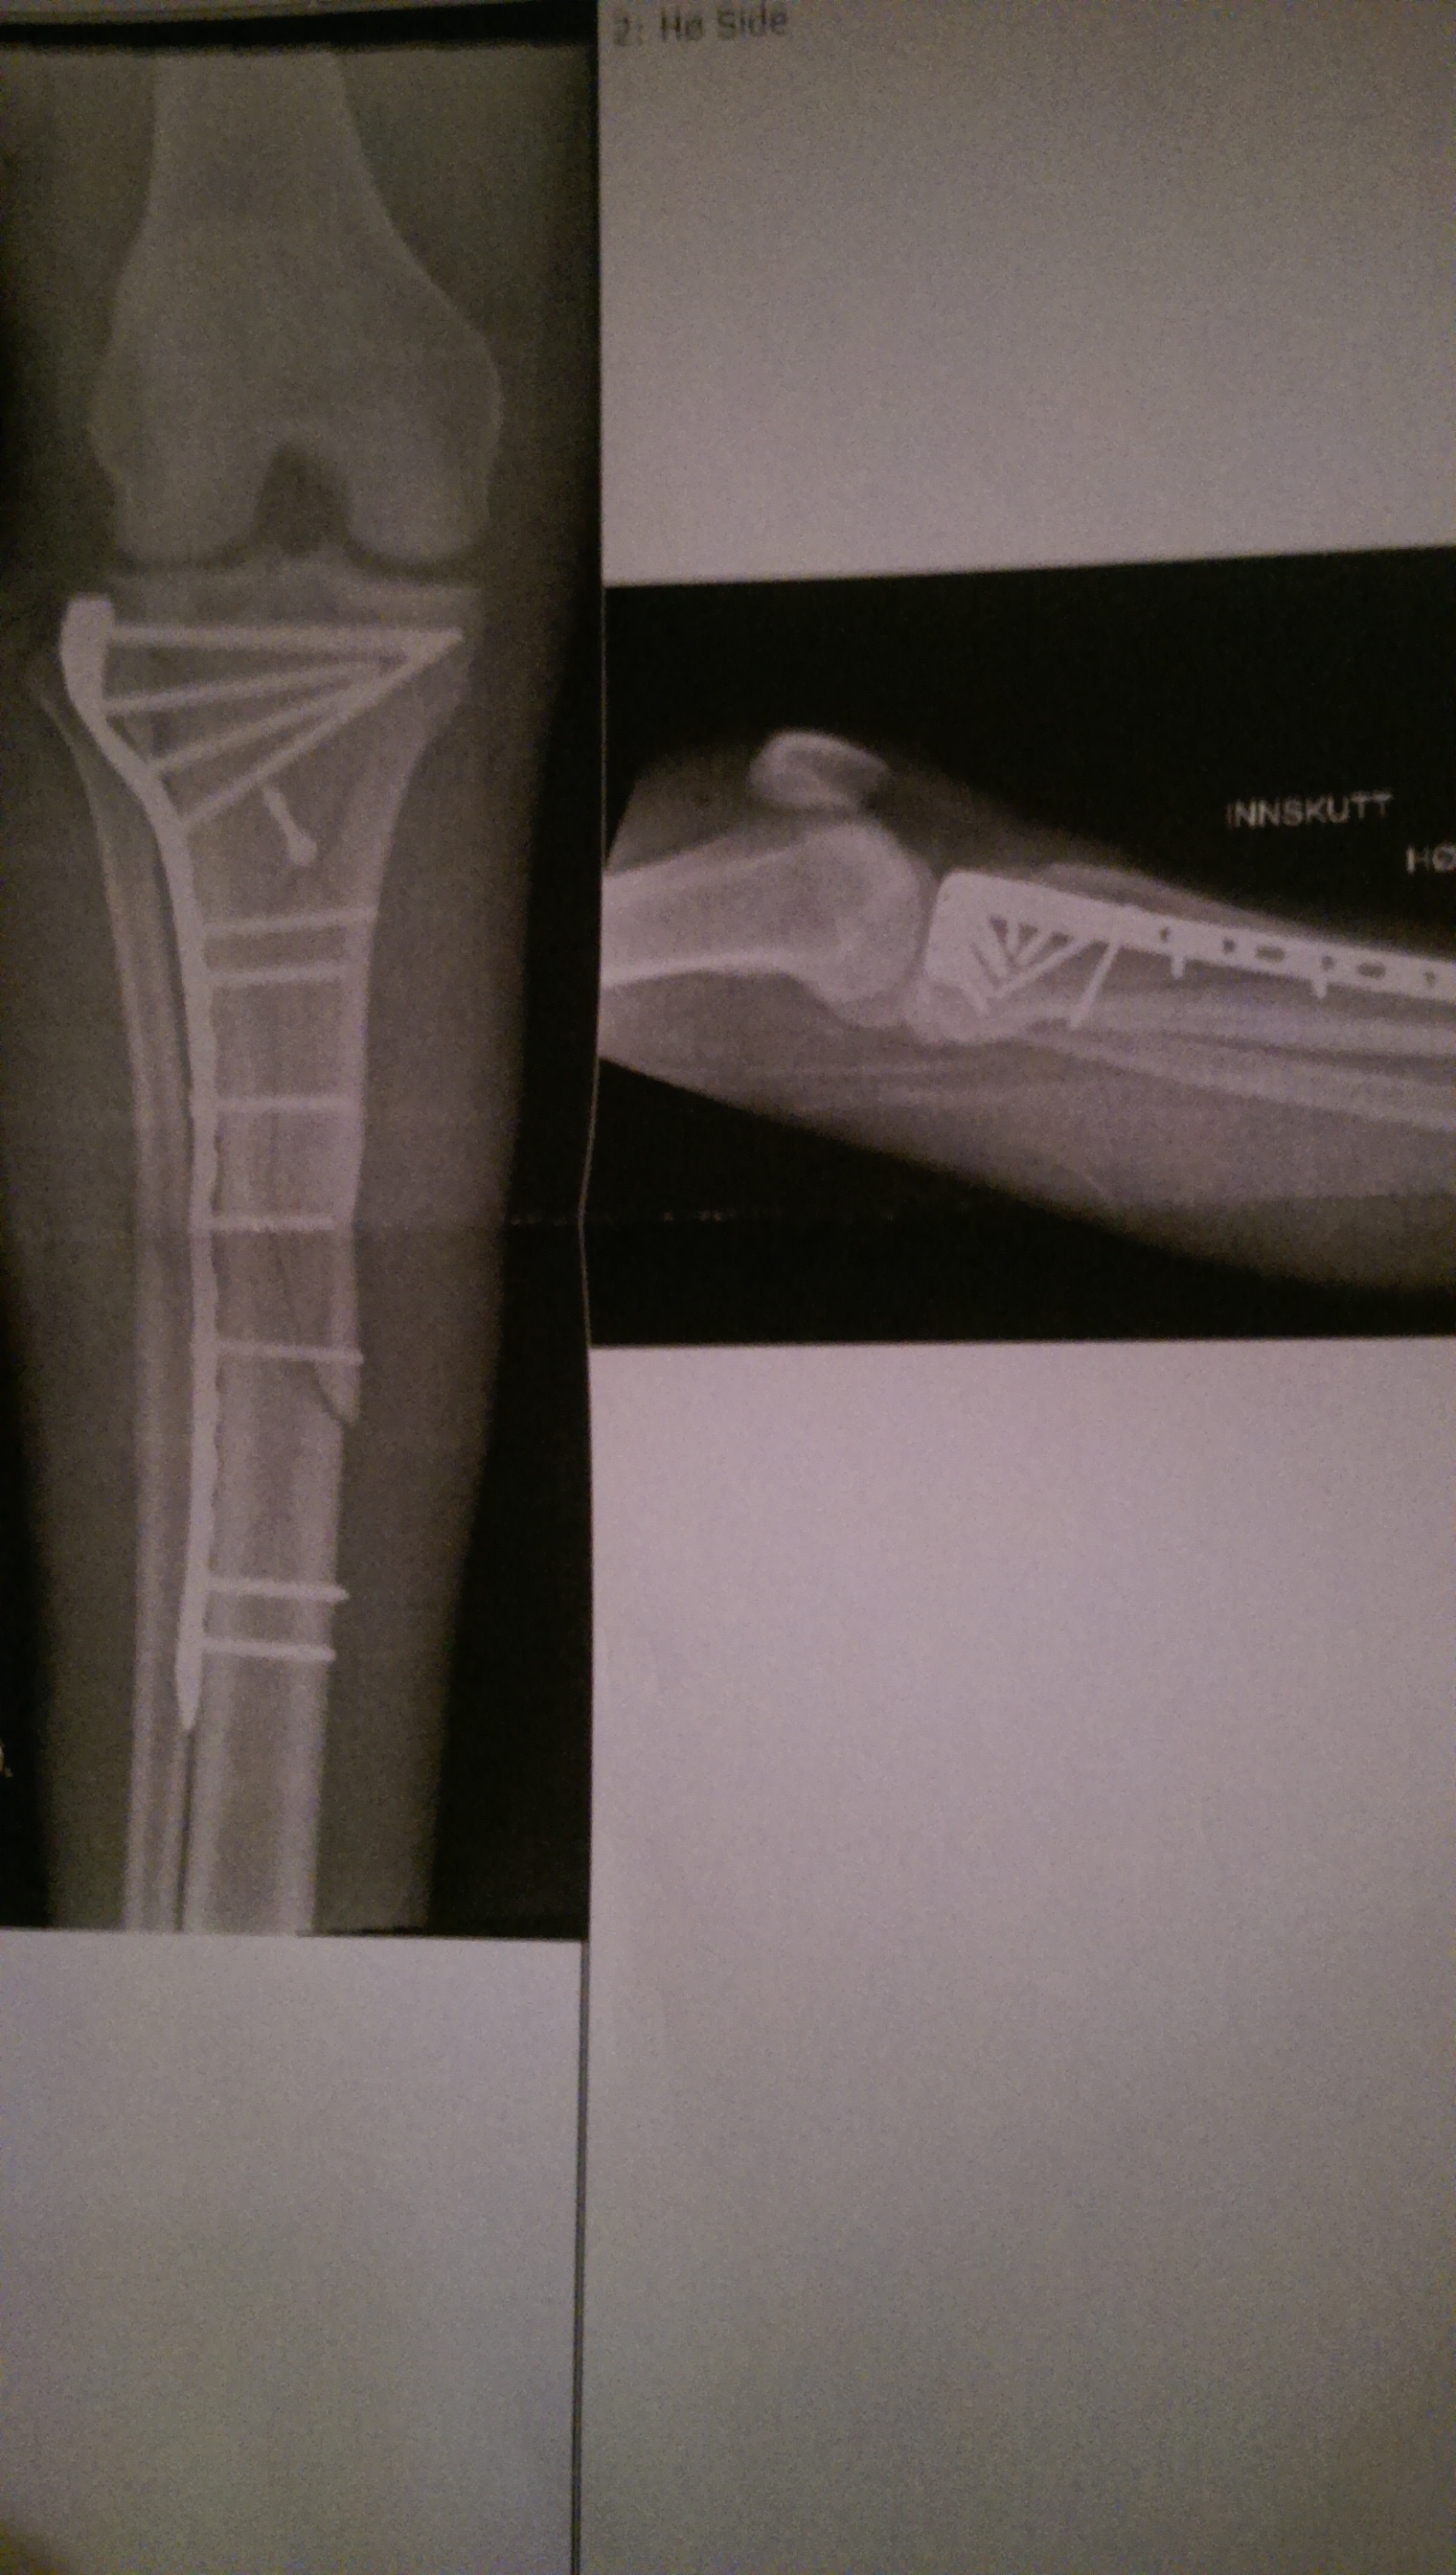

I was still high as a kite, but at least I could sort of focus and hear what people where saying to me. And it was not just pretty things I heard. Apparently the crash was more violent than I had thought, and the tibia was broken in several pieces starting at the boot cuff and ending right at the knee. Things did look quite bleak. To add insult to injury, I emptied the bottle I had just urinated in over myself. Never give open bottles to high people, they lack in balance and dexterity. Having been moved to a dry bed, I was rejoined by Andrea and left waiting for surgery.

The surgeons spent over four hours nailing all the bits back together, and I am convinced they did a thorough job. At least they did not skimp on screws. As is maybe obvious even to the not medically trained reader, that knee needs a bit of rest before it will be ready for action. To be precise, 6 weeks of absolutely no weight load at all, and a massive knee brace to take all side loads off as well. After that, we will see, but the surgeons sounded positive, giving me hope that there will be a biking season at some point in the future. Today, I was out of the house for the first time since Friday when I came home from the hospital, and did it ever feel so good to get a breath of fresh air!